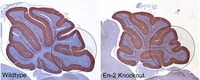

Musterbildung im Kleinhirn als Basis neuonaler Netzwerke (Oberdick et al, TINS 21:833 (1998)